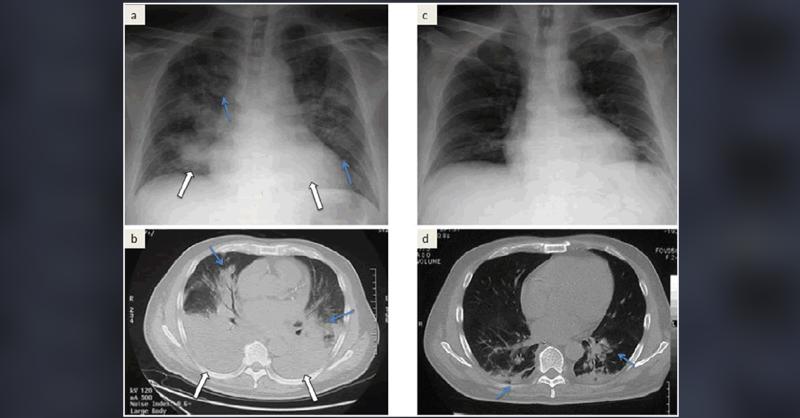

- Acute Promyelocytic Leukemia In An Adult Male With Unusual Radiological Findings

A 55-year-old male presented with bloody stool, leukocytosis, blast cells in peripheral blood, and thrombocytopenia. He had symptoms of general fatigue, appetite loss, and shortness of breath. He has Hypertension and a strong family history of stroke, coronary artery disease, and peripheral artery disease. His white blood cell count was 21,400/μl,